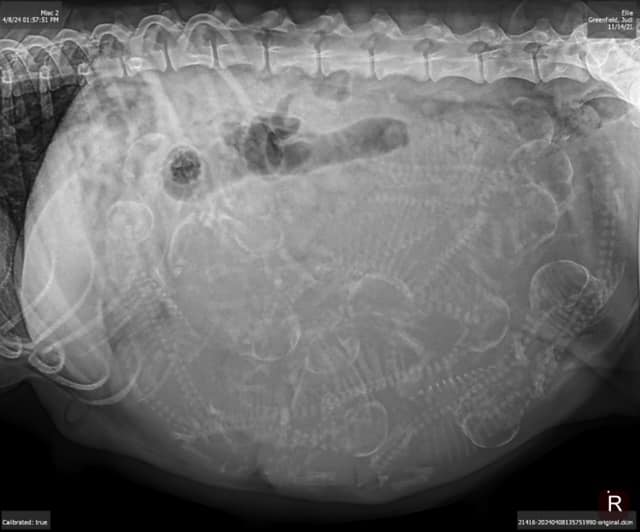

April 2024